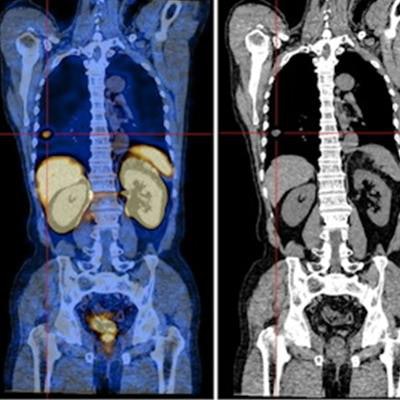

A 66-year-old patient with biochemical recurrence of prostate cancer. The patient's Gleason score was 7, and the PSA level was 3.14 ng/mL. (A) Whole-body planar Tc-99m MDP. (B) Whole-body planar Tc-99m PSMA and coronal SPECT/CT. Tc-99m PSMA-SPECT/CT helped identify lung metastasis (B, red arrow and cross). Image courtesy of Scientific Reports.An analysis revealed a sensitivity and specificity of 80% and 100% for Tc-99m PSMA-SPECT/CT and 72% and 81.6% for Tc-99m MDP-SPECT/CT, the researchers wrote.